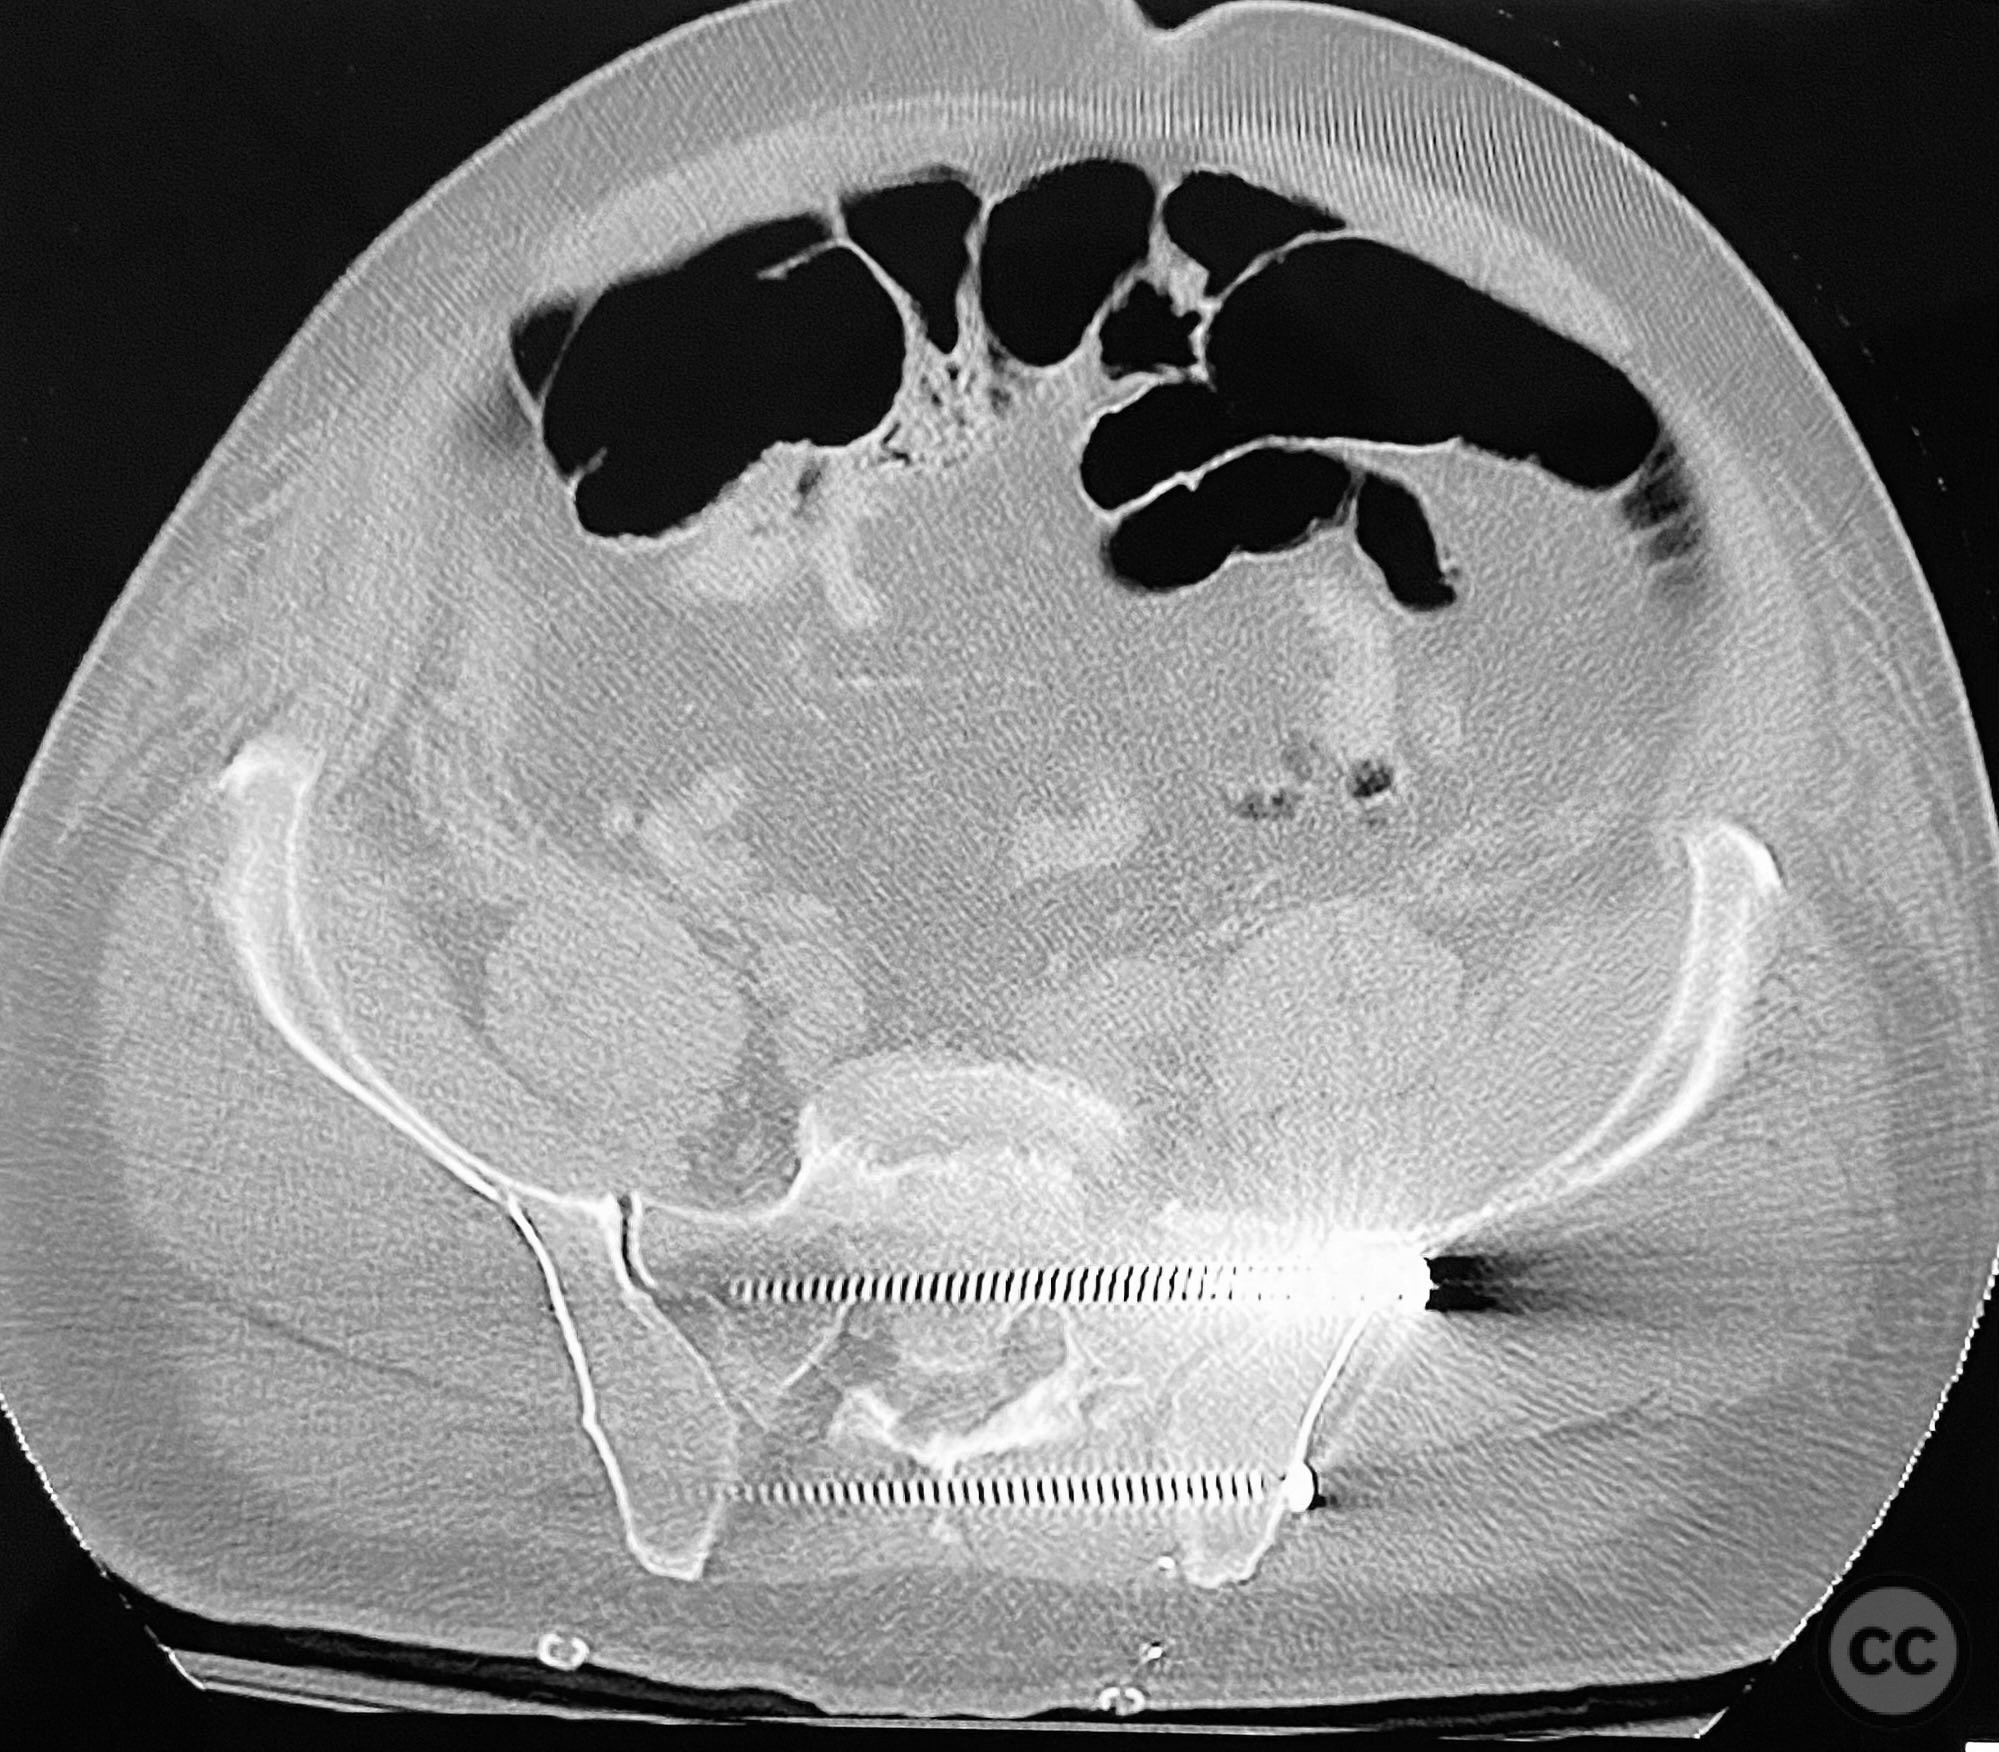

Clinical and radiological findings:  Middle-aged male with a high-energy pelvic ring injury, presenting with significant pain and mechanical instability. Initial radiographs demonstrated comminution and displacement of the posterior pelvic ring, including sacral fractures and disruption of the anterior ring at the pubic symphysis and rami. Application of a circumferential pelvic sheet provided partial reduction and improved comfort. No neurovascular deficits were noted. CT imaging confirmed a comminuted sacral fracture (AO/OTA 61-C1.3), with bilateral pubic rami fractures and symphyseal diastasis. The posterior elements demonstrated both vertical and rotational instability.

Anatomical surgical approach:  Posterior approach to the sacrum via a midline longitudinal incision, subperiosteal dissection to expose the dorsal sacral cortex and fracture lines. Direct reduction of the sacral fragments using clamps applied to the dorsal cortical edges, with intraoperative fluoroscopic guidance. Placement of iliosacral screws (non-cannulated, <130mm length due to implant availability at the time) across S1, supplemented by a posterior transiliac screw. For anterior fixation, a Pfannenstiel incision was used to expose the symphysis pubis and superior pubic rami; reduction achieved with pointed reduction forceps, followed by plate osteosynthesis of the symphysis and screw fixation of the rami as indicated.

The staged approach allowed direct assessment and refinement of posterior reduction using dorsal cortical landmarks, which was critical given the comminution and displacement pattern. The absence of long cannulated screws limited optimal iliosacral screw placement; screws were contained within the osseous fixation pathway but not ideally positioned for maximal safety or precision by contemporary standards. Anterior ring stabilization was performed after confirming satisfactory posterior reduction on postoperative CT. The sequence addressed both vertical and rotational instability, but implant limitations may have increased risk for suboptimal fixation or neurovascular compromise. In current practice, advanced imaging, navigation, and longer cannulated screws would be utilized to optimize screw trajectory and safety.

Orthopaedic implants used:   6.5mm non-cannulated iliosacral screws (<130mm), posterior transiliac screw, anterior symphyseal plate, cortical screws for pubic rami